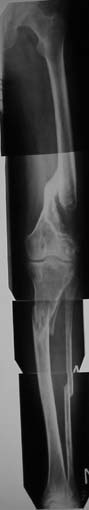

Пациенту 42 года. Травма 4 года назад. "Мостик" на бедре вроде бы держит, но без брейса не ходит + постоянно костыли. Ко всему рубцы в области коленного сустава, качательные (3-5 гр.) в коленном и укорочение бедра 5 см, голени 1-1,5.

На этом ось практически не изменена, только укорочение.

Скорее соглашусь с Е.Чекашкиным, и для решения вопроса о плане лечения крайне необходимо четко представлять анатомо- топографические характеристики четырехглавой мышцы. ЭМГ нужна, но важнее контрастная рентгенография, поскольку при укорочении брюшка прямой и промежуточной мышц на 40% за счет атрофии и при наличии фиброзных изменений ( а они есть однозначно), любые операции по увеличению объема движений в коленном суставе практически бесполезны.Кроме того, необходимо четко представлять состояние праартикулярных тканей( УЗИ, КТ,МРТ)и кости в зоне консолидации (КТ)Кстати, брюшко не может быть" удлиненным по сравнению с укороченной костью", поскольку за 4 года ретракция и атрофия сделали свое дело. При сохранении достаточной длины и тлщины мышечного брюшка и хорошем состоянии параартикулярных тканей можно попытаться увеличить объем движений в суставе. В противном случае - удлинить бедро . На представленном снимке не совсем ясна ситуация в зоне консолидации.Насколько прочно сращение?

На рентгенограмме прямая и промежуточная мышцы больной с врожденным укорочением бедра на 7 см( для примера). Нормальная ситуация.